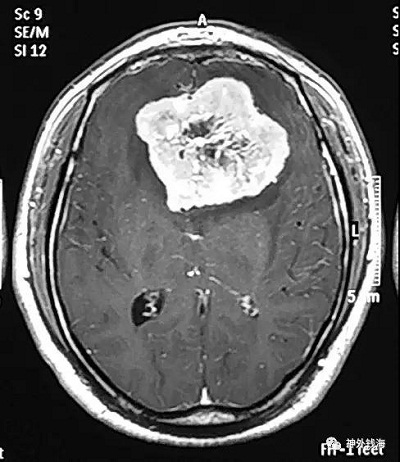

在临床工作中,我经常遇见这样的情况:患者视力一直不好,在眼科检查治疗了很长时间也不见效,眼科也的确没有发现异常情况。还有的患者月经紊乱,或者不孕不育,在妇产科及内分泌科治疗了一段时间,也是没有效果。后查了头部的核磁共振,才发现原来病因在颅内,鞍区已经有了一个很大的肿瘤。手术切除肿瘤以后,原来的眼睛或内分泌问题也逐步恢复了。这就是特别需要引起重视的,即颅内肿瘤可能表现为眼科或妇产科、内分泌科的疾病,如果忽略了头部检查,则可能遗漏了根本的病因,因而疗效只会是暂时的,或者是“久治不愈”。

尽管颅内肿瘤相对于眼科疾病、妇产科疾病及内分泌科疾病的发病率低,相对少见,但是在神经外科住院患者中,很大一部分患者以此为主要症状或首发症状。磁共振检查对人基本无损伤,无放射性,可以有效检查出上述颅内疾病。

首都医科大学三博脑科医院神经外科钱海特别提示眼科、妇产科及内分泌科的患者,如果遇到上面所说的情况,特别是伴有头痛的患者,请在医生指导下进行头部磁共振检查,可能会找到疾病的源头,从而达到满意的疗效。